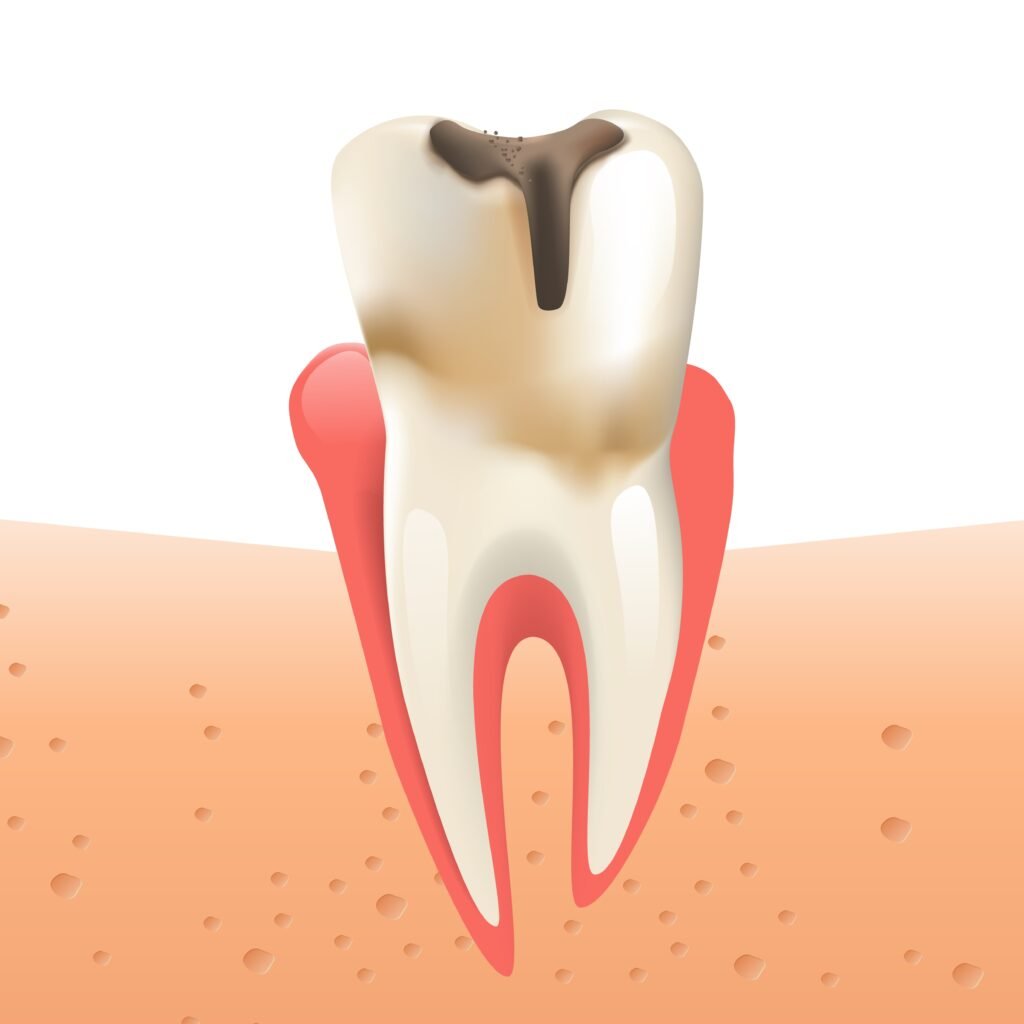

Any shift or disturbance in the equilibrium of the oral microflora can tilt the scales in favor of oral infections, cavities, periodontal problems, gum inflammation, persistent bad breath and other oral diseases.

Integrating a balanced diet with lactic acid bacteria helps neutralize the acidity of the mouth, thus inhibiting the proliferation of the bacteria responsible for the onset of dental caries and periodontal disease.